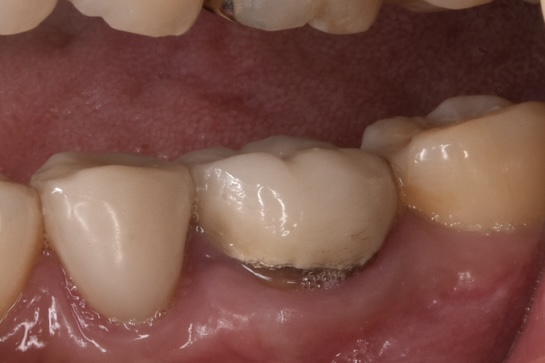

モニター様②

奥歯のやりかえです。真ん中に写っている左下奥歯(左側下顎第一大臼歯)の再治療です。神経治療からやり直しています。*色彩セラミックプラン